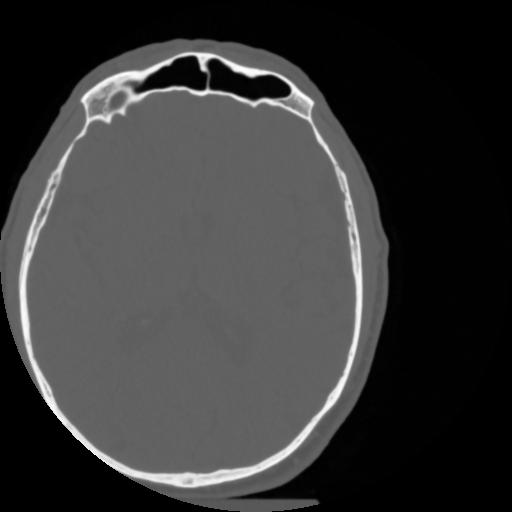

4 CEREBRO,,Vol,0.5,CEREBRO,,